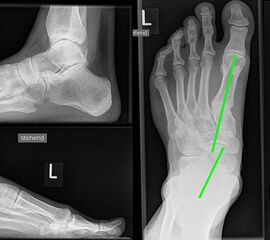

Röntgenaufnahmen dienen vor allem zum Ausschluss einer knöchernen Verletzung und umfassen Aufnahmen des Sprunggelenks anterior-posterior, lateral und 20° Innenrotation (Mortise view). Gehaltene Aufnahmen werden bei der Akutverletzung nicht empfohlen, da sie die Behandlungsstrategie nicht beeinflussen, keine zusätzlichen Informationen liefern und das Risiko besteht die verletzten Strukturen weiter zu schädigen 2.

Bei einer chronischen Instabilität können gehaltene Aufnahmen eine vermehrte mediale Aufklappbarkeit zeigen, wobei falsch negative Befunde möglich sind 8. Die höchste Zuverlässigkeit liefert die dynamische Untersuchung in Narkose 2.

Bei Insuffizienz der tibionavicularen Bandanteile oder des Spring-Ligaments zeigen die konventionellen Aufnahmen eine Konstellation wie bei einer Tibialis posterior Insuffizienz mit Vorfußabduktion, eingesunkenem Längsgewölbe und vermehrtem Rückfußvalgus (Abbildung 3).